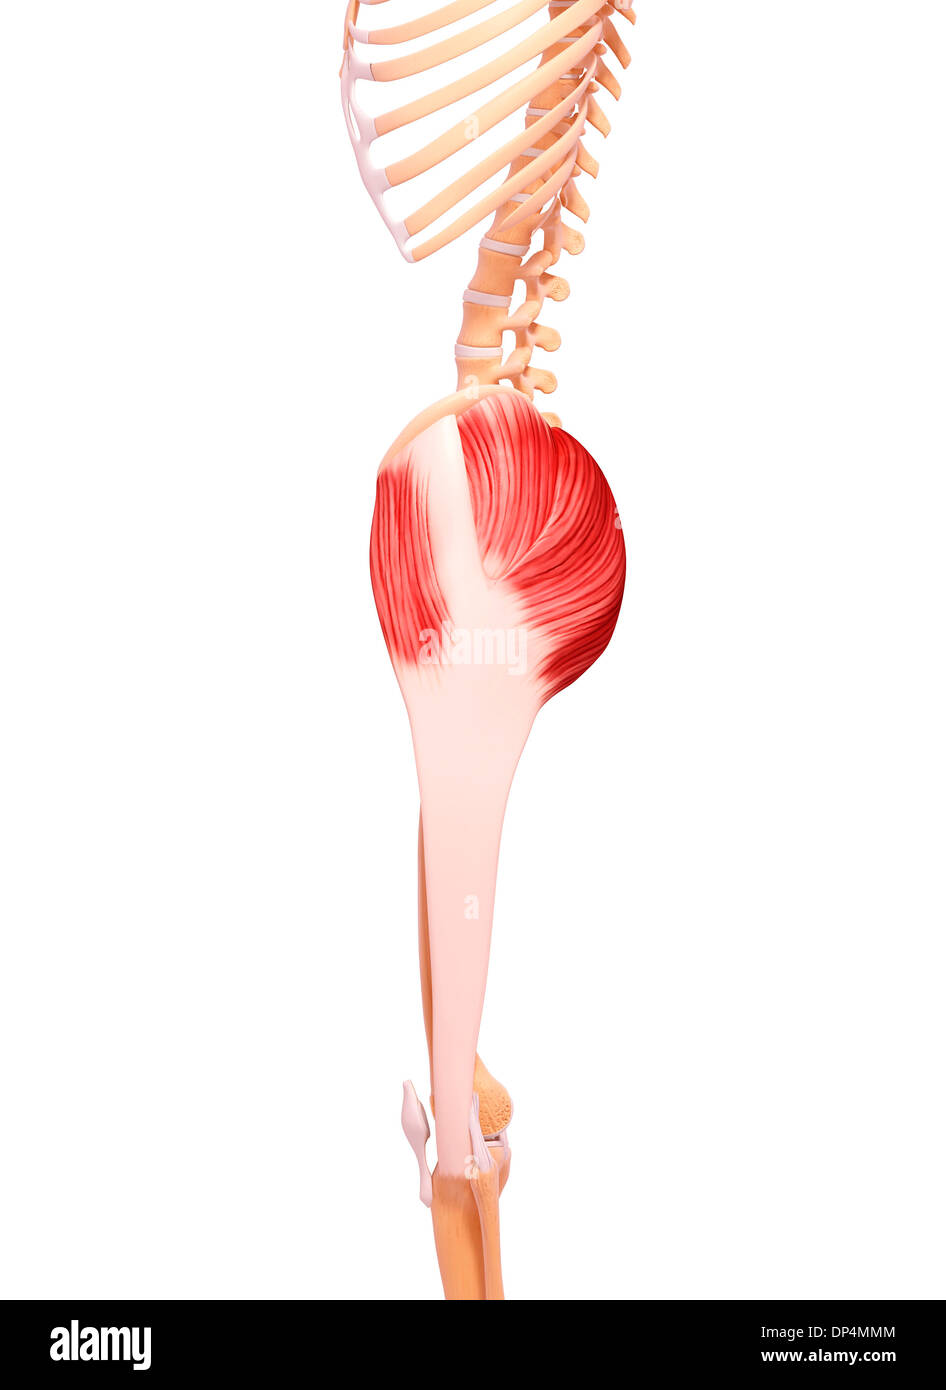

Human musculature, artwork Stock Photohttps://www.alamy.com/image-license-details/?v=1https://www.alamy.com/human-musculature-artwork-image65257604.html

Human musculature, artwork Stock Photohttps://www.alamy.com/image-license-details/?v=1https://www.alamy.com/human-musculature-artwork-image65257604.htmlRFDP4MMM–Human musculature, artwork